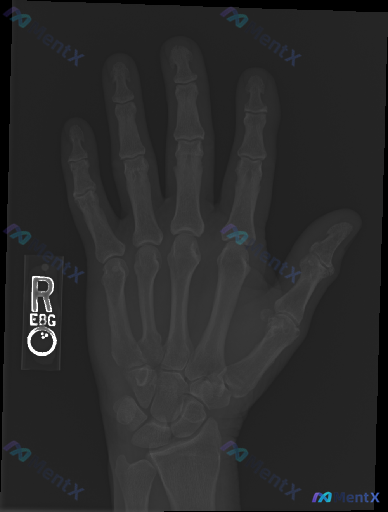

一份右手正位X光片,常规影像学评估结果如下:

- 各指骨、掌骨、腕骨骨皮质连续性未见明显中断,无明确骨折线、隐匿性骨折征象或骨膜反应;

- 各掌指、指间关节及腕骨间关节间隙基本正常,对位良好,无脱位半脱位;

- 骨质密度分布均匀,未见明显骨质疏松、骨质硬化、侵蚀或破坏;

- 软组织影厚度适中,未见明显肿胀、积气,也未见确切的不透X线异物或钙化灶;

- 骨骺已闭合,无明显退行性骨赘或先天变异。